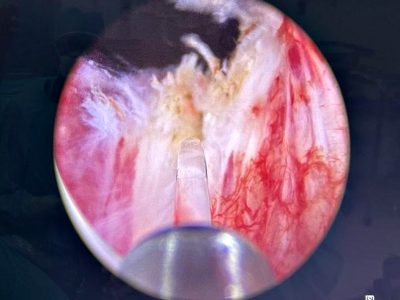

Nefrolitotomía Percutánea Con técnica Miniperc

Miniperc, es una técnica eficaz y segura, con una mínima incisión en la piel, para el tratamiento de las piedras en el riñón de pequeño y mediano tamaño.

El riesgo de sangrado, las posibles complicaciones y el tiempo de hospitalización es menor que con otras técnicas de nefrolitotomía percutánea.

Los calibres de los tractos de acceso se alejan considerablemente del calibre de la cirugía percutánea clásica, disminuyendo asi los daños generados en el parénquima renal.

El nefroscopio minipercutáneo es recomendable para el tratamiento de piedras de 1 hasta 3 cm, tiene un canal de trabajo que permite el paso de instrumentos de hasta 6.7 french.

Su diseño compacto y la ventaja de realizar incisiones mas pequeñas permiten una recuperación mas rápida y la reducción de complicaciones postoperatorias.

Tras la incisión cutánea, se ensancha el acceso con un solo dilatador hasta el punto de que la vaina se pueda deslizar hasta el riñón, ya no es necesario recurrir a los dilatadores telescópicos o los dilatadores de varios tamaños.

La miniperc implica, además de la reducción del diámetro del tracto externo y del instrumento de trabajo (nefroscopio), otras modificaciones en la técnica de la litotricia en beneficio de la comodidad postoperatoria del paciente.

Entre estas modificaciones se encuentran el uso de tecnología láser para la fragmentación o pulverización de cálculos, la disminución de los elementos de extracción, la reducción del calibre de la nefrostomia (abertura desde el exterior del cuerpo hasta la pelvis renal) y diferente estrategia de salida.

Los sistemas láser que utilizan fibras de tulio o de holmio de alta potencia y alta frecuencia pueden optimizar aún más los resultados.